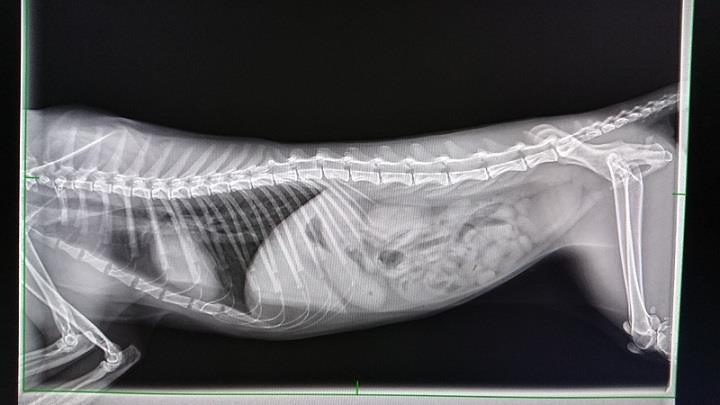

且此次回所全身、頭部搖晃不停,

先行就醫,檢測應為農藥中毒,

影響神經所致。

動物近況說明: 經過治療後,搖晃與發抖的狀況已經緩和許多,情緒也逐漸穩定,但依舊會顫抖不止,仍然要繼續治療與觀察。